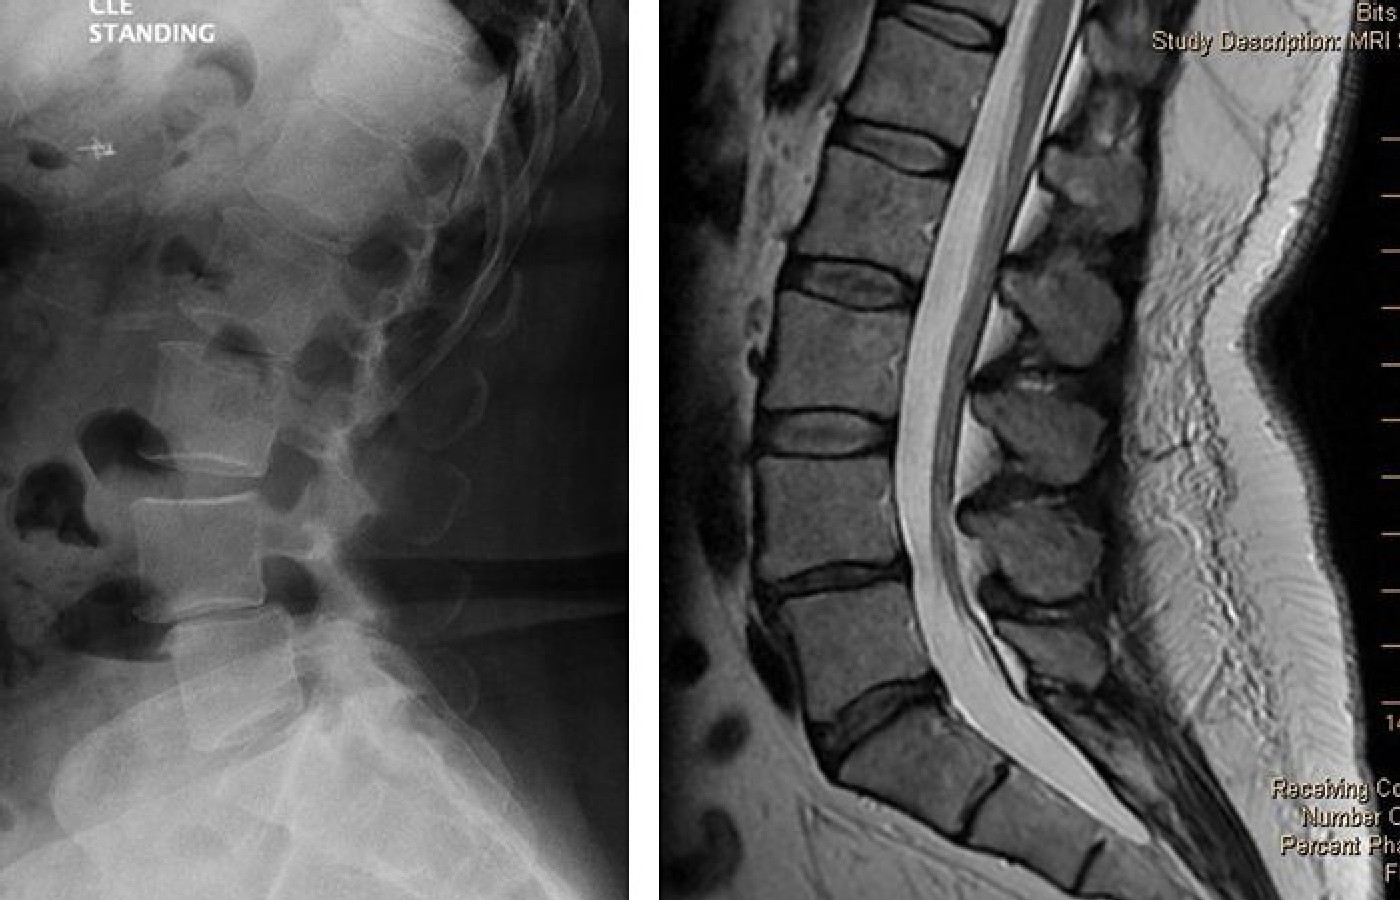

Review the routine radiograph in Figure 1A [left image]. The patient has a spondylolisthesis at L4-L5. Now review the MR image of the same patient in Figure 1B [right image]. Where did the spondylolisthesis go? The answer? Instability allowed the spondylolisthesis to reduce.

The routine radiograph was taken with the patient standing, bearing his body weight. In that position, gravity assists the unstable L4 segment in moving anteriorly. The MR scan was taken with the patient supine, bearing a much lower degree of body weight. Gravity is less of a factor here, and the L4 segment moves posteriorly, closer to its normal position.

From reviewing the images in Figures 1A and 1B, common sense would suggest that when a spondylolisthesis is identified on a standing lateral view, an additional lateral view taken with the patient supine could be helpful. The goal is to detect the transition of the unstable segment, similar to the transition seen in Figures 1A and 1B.